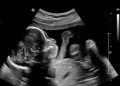

Enam Minggu Pertama. Statistik janin Anda di minggu ini.

Akhir minggu ke-6, sel telur yang dibuahi sperma akan mulai membentuk segerombolan sel serupa bola yang disebut blastocyst. Blastocyst ini...